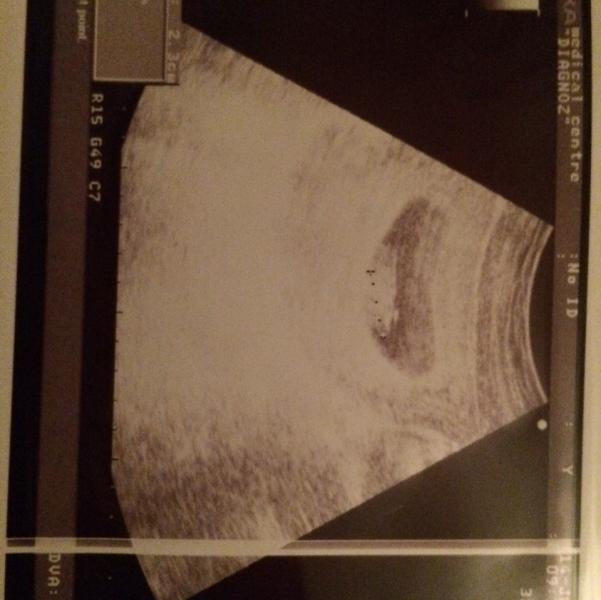

Сегодня был самый тяжелый и волнительный день для меня первое узи 🙏🏻🌸 я до последнего не могла расслабиться пока не услышала ТУК-ТУК-ТУК моего маленького😭🙏🏻 о Аллагь как я была счастлива😍 мой сладенький развивается по сроку, с ним Альхамдулиллах все хорошо🙏🏻❤️ Дай Аллагь каждой испытать это счастье🙏🏻❤️🌸

@_subhana_, да сердцебиение тоже слышно было и показали как стучит сердечко... Да пойду не думаю что это прям очень вредно... На сколько мне известно с 7-8 недели уже можно услышать биение сердца...